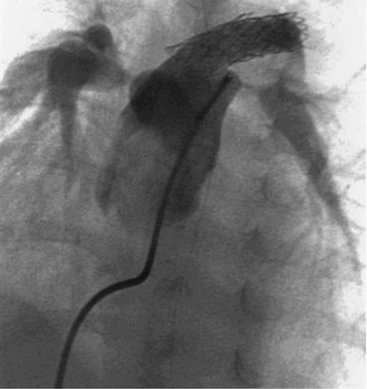

The anomalies addressed here include anomalous coronary artery origins from the pulmonary artery instead of from the aorta; some anomalous aortic origins of coronary arteries; fistulas of a coronary arteries; and congenital atresia of the left main coronary artery.242,446,456,588

Coronary Artery Fistulas

Fistulas are the most common type of hemodynamically significant coronary anomalies; they can be congenital or acquired. Fistulas can be isolated or can occur in combination with other heart defects.242 They can involve the right (most common), left, or both coronary arteries.497 The fistulous connection can involve a coronary vein, a vena cava, a chamber of the heart, a great artery, pulmonary vessels, or an aorto-left ventricular tunnel.242,446,456,497

A fistula produces shunting of flow from the higher pressure to the lower pressure end of the fistula. The most common type of fistula is a coronary artery to right-heart structure (arteriovenous) fistula, which results in a left-to-right shunt.497 When the fistula connects to a left heart structure (arterioarterial fistula) there may be runoff from the aorta during low pressure phases of the cardiac cycle; this runoff can increase left ventricular volume load.497

The ECG and chest radiograph may be normal or may provide suggestive but nonspecific evidence. Echocardiography may establish the diagnosis, particularly if the fistula is large. Cardiac catheterization can provide the definitive diagnosis with aortography and selective coronary angiograms.336,497 Endocarditis and aneurysm with rupture have been reported with this lesion.456

In rare cases, spontaneous closure of a fistula has been reported. Intervention is recommended only if symptoms are present. In some cases coil occlusion of the fistula is possible during cardiac catheterization. Otherwise, surgery is performed through a median sternotomy incision and usually requires cardiopulmonary bypass. The fistula is identified, approached through the vessel or chamber, and sutures are used to close the connection. Without treatment the natural history of these defects has not been clearly determined, but surgical and hospital mortality, rate of complications, and late mortality are all very low.497